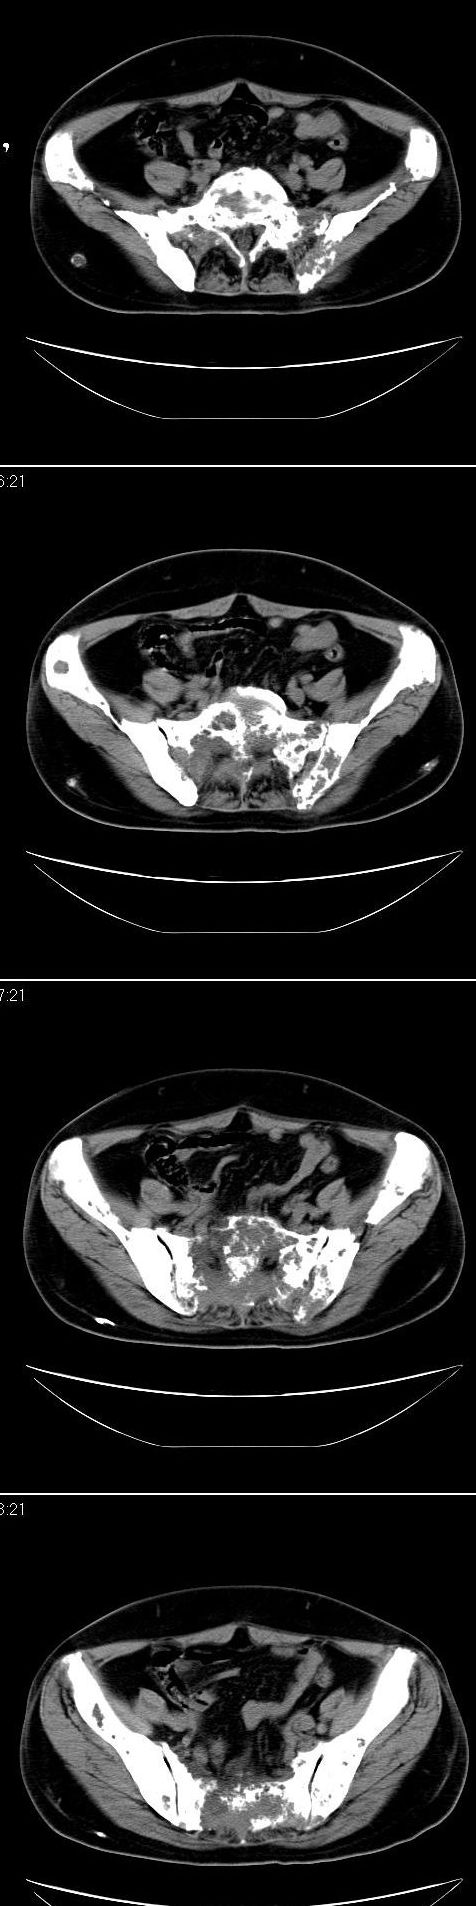

标题: CT13121:女,54岁。乳腺癌术后8年。 [打印本页]

女,54岁。乳腺癌术后8年。现感觉左腿酸困不适,并向下放散。左腿僵硬,不由自主。

典型溶骨型转移瘤。

骨盆及腰椎多发性溶骨性转移瘤.

成骨及融骨转移。

结合病史考虑乳腺癌术后多骨骨转移。

支持 骨转移瘤---混合型以溶骨为主

结合临床考虑多骨多灶性溶、成骨性转移。